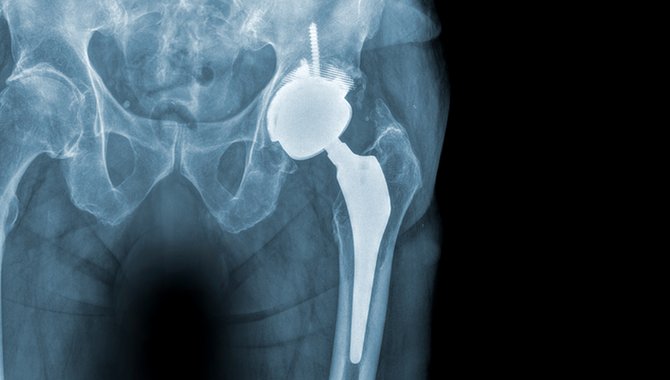

Das Kniegelenk ist das grösste Gelenk im menschlichen Körper. Es ist so individuell, wie der Mensch selbst: Jede Beinachse ist …